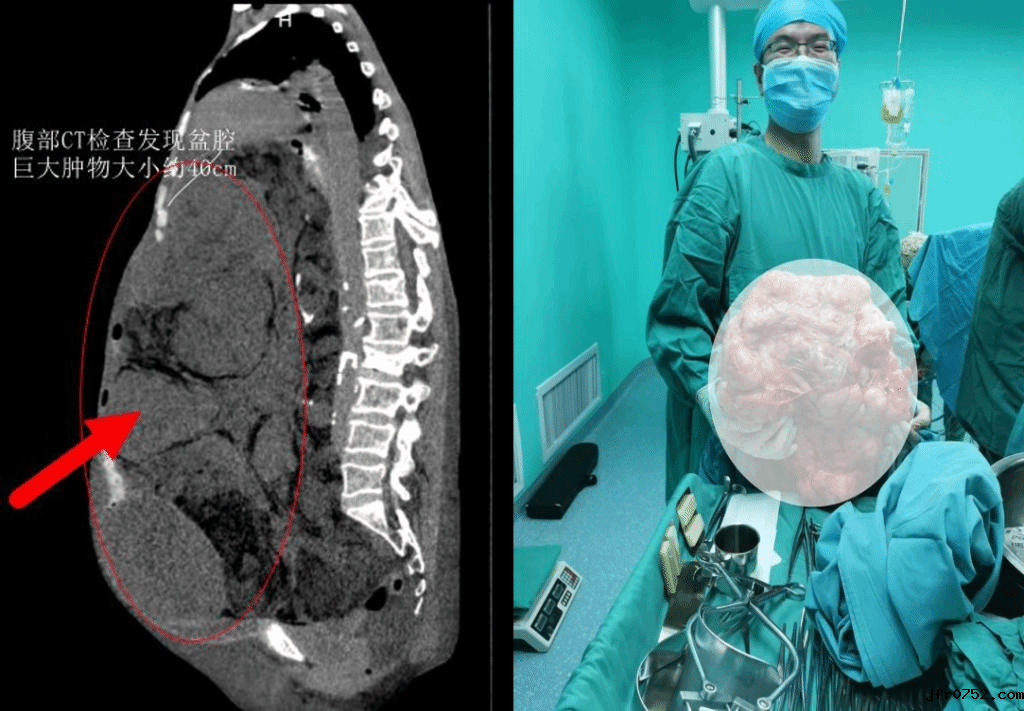

家人带着马阿姨到多家医院就诊,医生均不敢贸然行手术治疗,后辗转来到伟德官网下app官方网站妇瘤二病区诊治。通过腹部CT检查发现盆腔巨大肿物,大小约40cm,患者无法平卧,有心脏病、肺功能下降、下肢静脉血栓、电解质紊乱、贫血等症状。

为提高手术成功率,医院决定进行多学科协作诊治,该手术由妇瘤病院常务副院长李东红、妇瘤病院二病区主任田小飞、普外科主任马龙安主持,来自手术麻醉科、ICU、护理部的专家与田小飞主任的医护团队进行了充分的术前讨论,制定个性化治疗方案、全周期护理措施,对术中可能出现的各种并发症及风险做好了防范预案。经过积极的术前准备,在手术麻醉科党晓东主任团队的协作下,所有医护人员紧密配合,分工明确,力求把损伤和风险降到最小。术中缓慢抽出淡黄色液体约2000ml后,成功切除大小45cm×30cm,重达40斤的腹盆腔巨大肿瘤。彻底摆脱了腹部重负的马阿姨目前恢复良好。